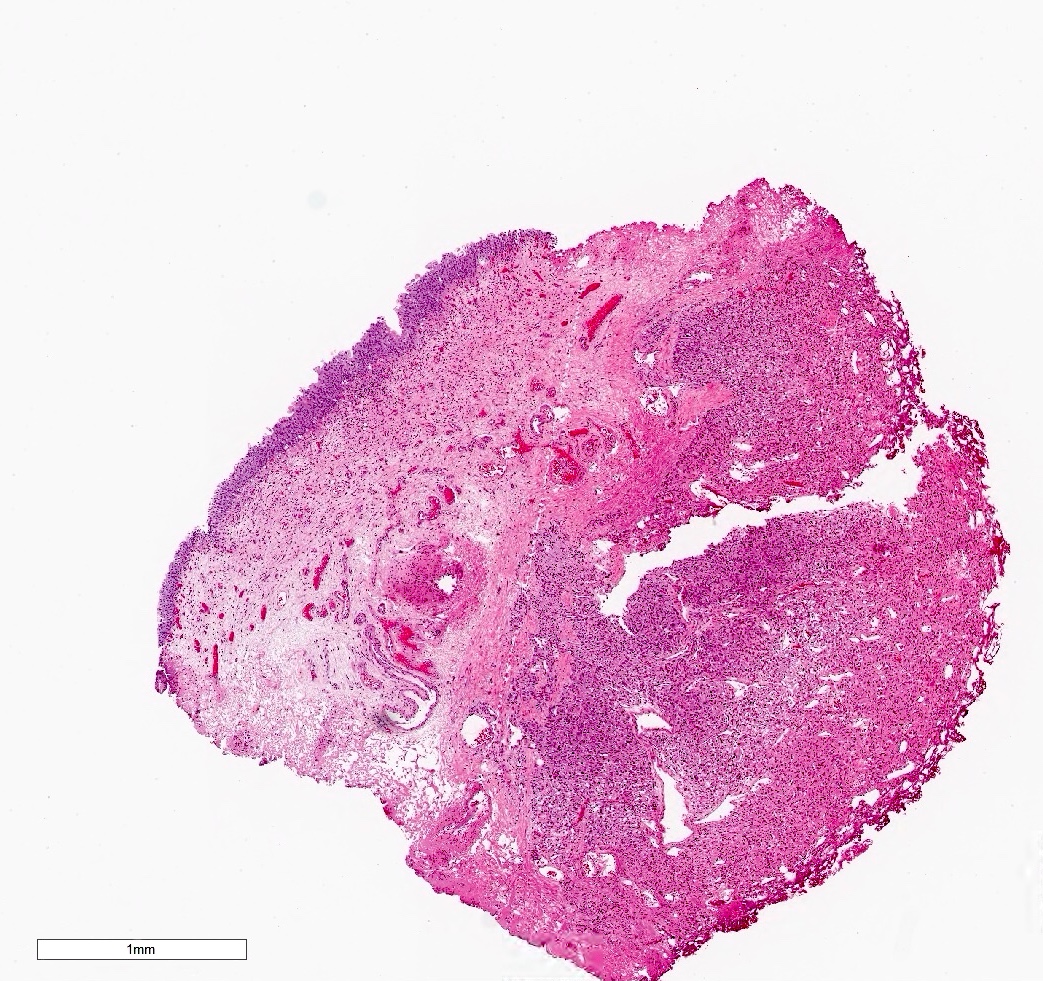

Gross description

- Genitourinary paragangliomas are typically tan-pink to violaceous, encapsulated and firm (Abdom Radiol (NY) 2022;47:1414, Abdom Radiol (NY) 2022;47:4032, BMC Urol 2023;23:21)

- Bladder paragangliomas are often submucosal or intramural and less frequently subserosal, with size at diagnosis up to 9.1 cm (mean: 3.9 cm)

- Small bladder paragangliomas: typically well circumscribed, round ovoid and homogeneous

- Larger bladder paragangliomas: usually more complex appearance with lobulation, peri and intratumoral vascularization and cystic / necrotic / hemorrhagic areas

Gross images

Microscopic (histologic) description

Microscopic (histologic) images

Contributed by Theodorus H. van der Kwast, M.D., Ph.D., Michelle R. Downes, M.D., Debra L. Zynger, M.D. and David Cohen, M.B.B.Ch., M.D.